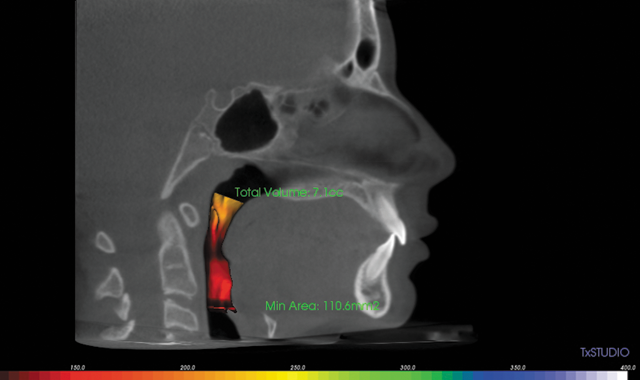

Dr. Kaspers (Kaspers Orthodontics in Northbrook, Ill.) decided to utilize a Herbst appliance calibrated to stimulate growth of the mandible to correct the skeletal Class II asymmetry and improve her constricted airway. After treatment, her total volume increased to 14.4 cc from 7.1 cc.